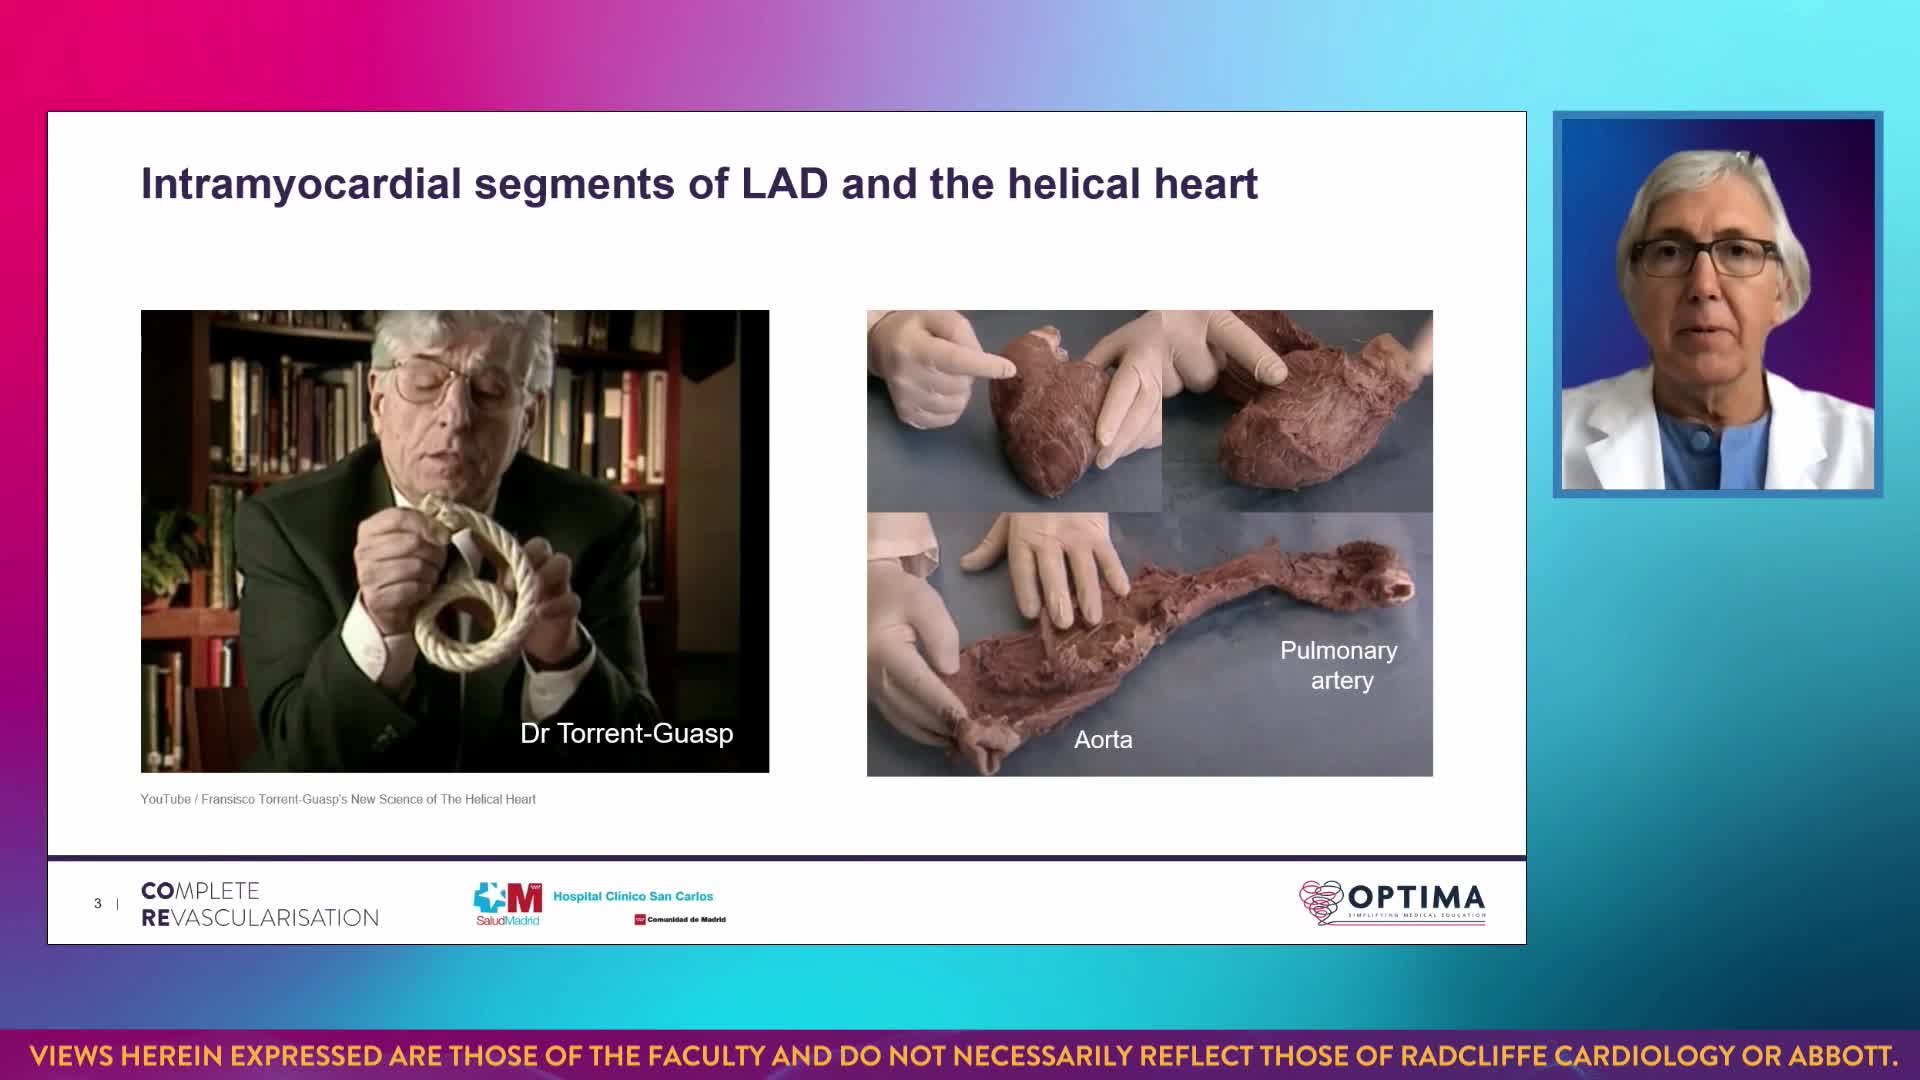

Session 1: Pre-procedure planning – are we lost without a map?